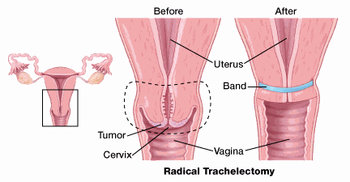

In a recent study in the journal cancer epidemiology, biomarkers and prevention had found that women who. Cryosurgery this treatment kills the cancer cells by freezing them. Ad learn more about a treatment option for advanced cervical cancer.

Treatment options include radiation therapy with or without chemo to try to slow the growth of the cancer or help relieve symptoms. Foods high in vitamin c, selenium, carotenoids, and vitamin e. Most standard chemo regimens include a.